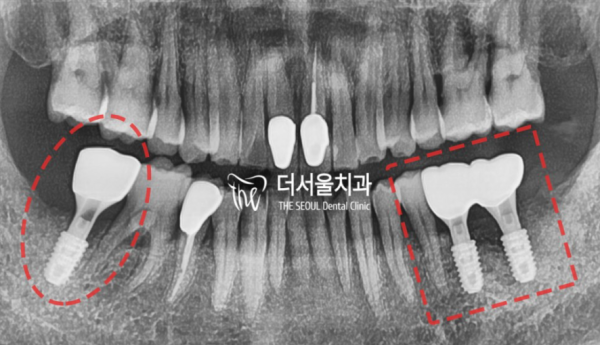

4663ae6bbd1cc5bef1a29e85d7ece520_1682772225_4933.png

기존에 뼈가 많이 퇴축되어 있었던 부분은 골유도재생술을 진행하고

임플란트가 진행되었습니다.

위에 보이시는 것 처럼 사랑니당일 발치 후 임플란트가 총 3개 심어졌습니다.

뼈가 잘 아물은 4개월 후 지르코니아 크라운으로 치료가 마무리되었답니다.